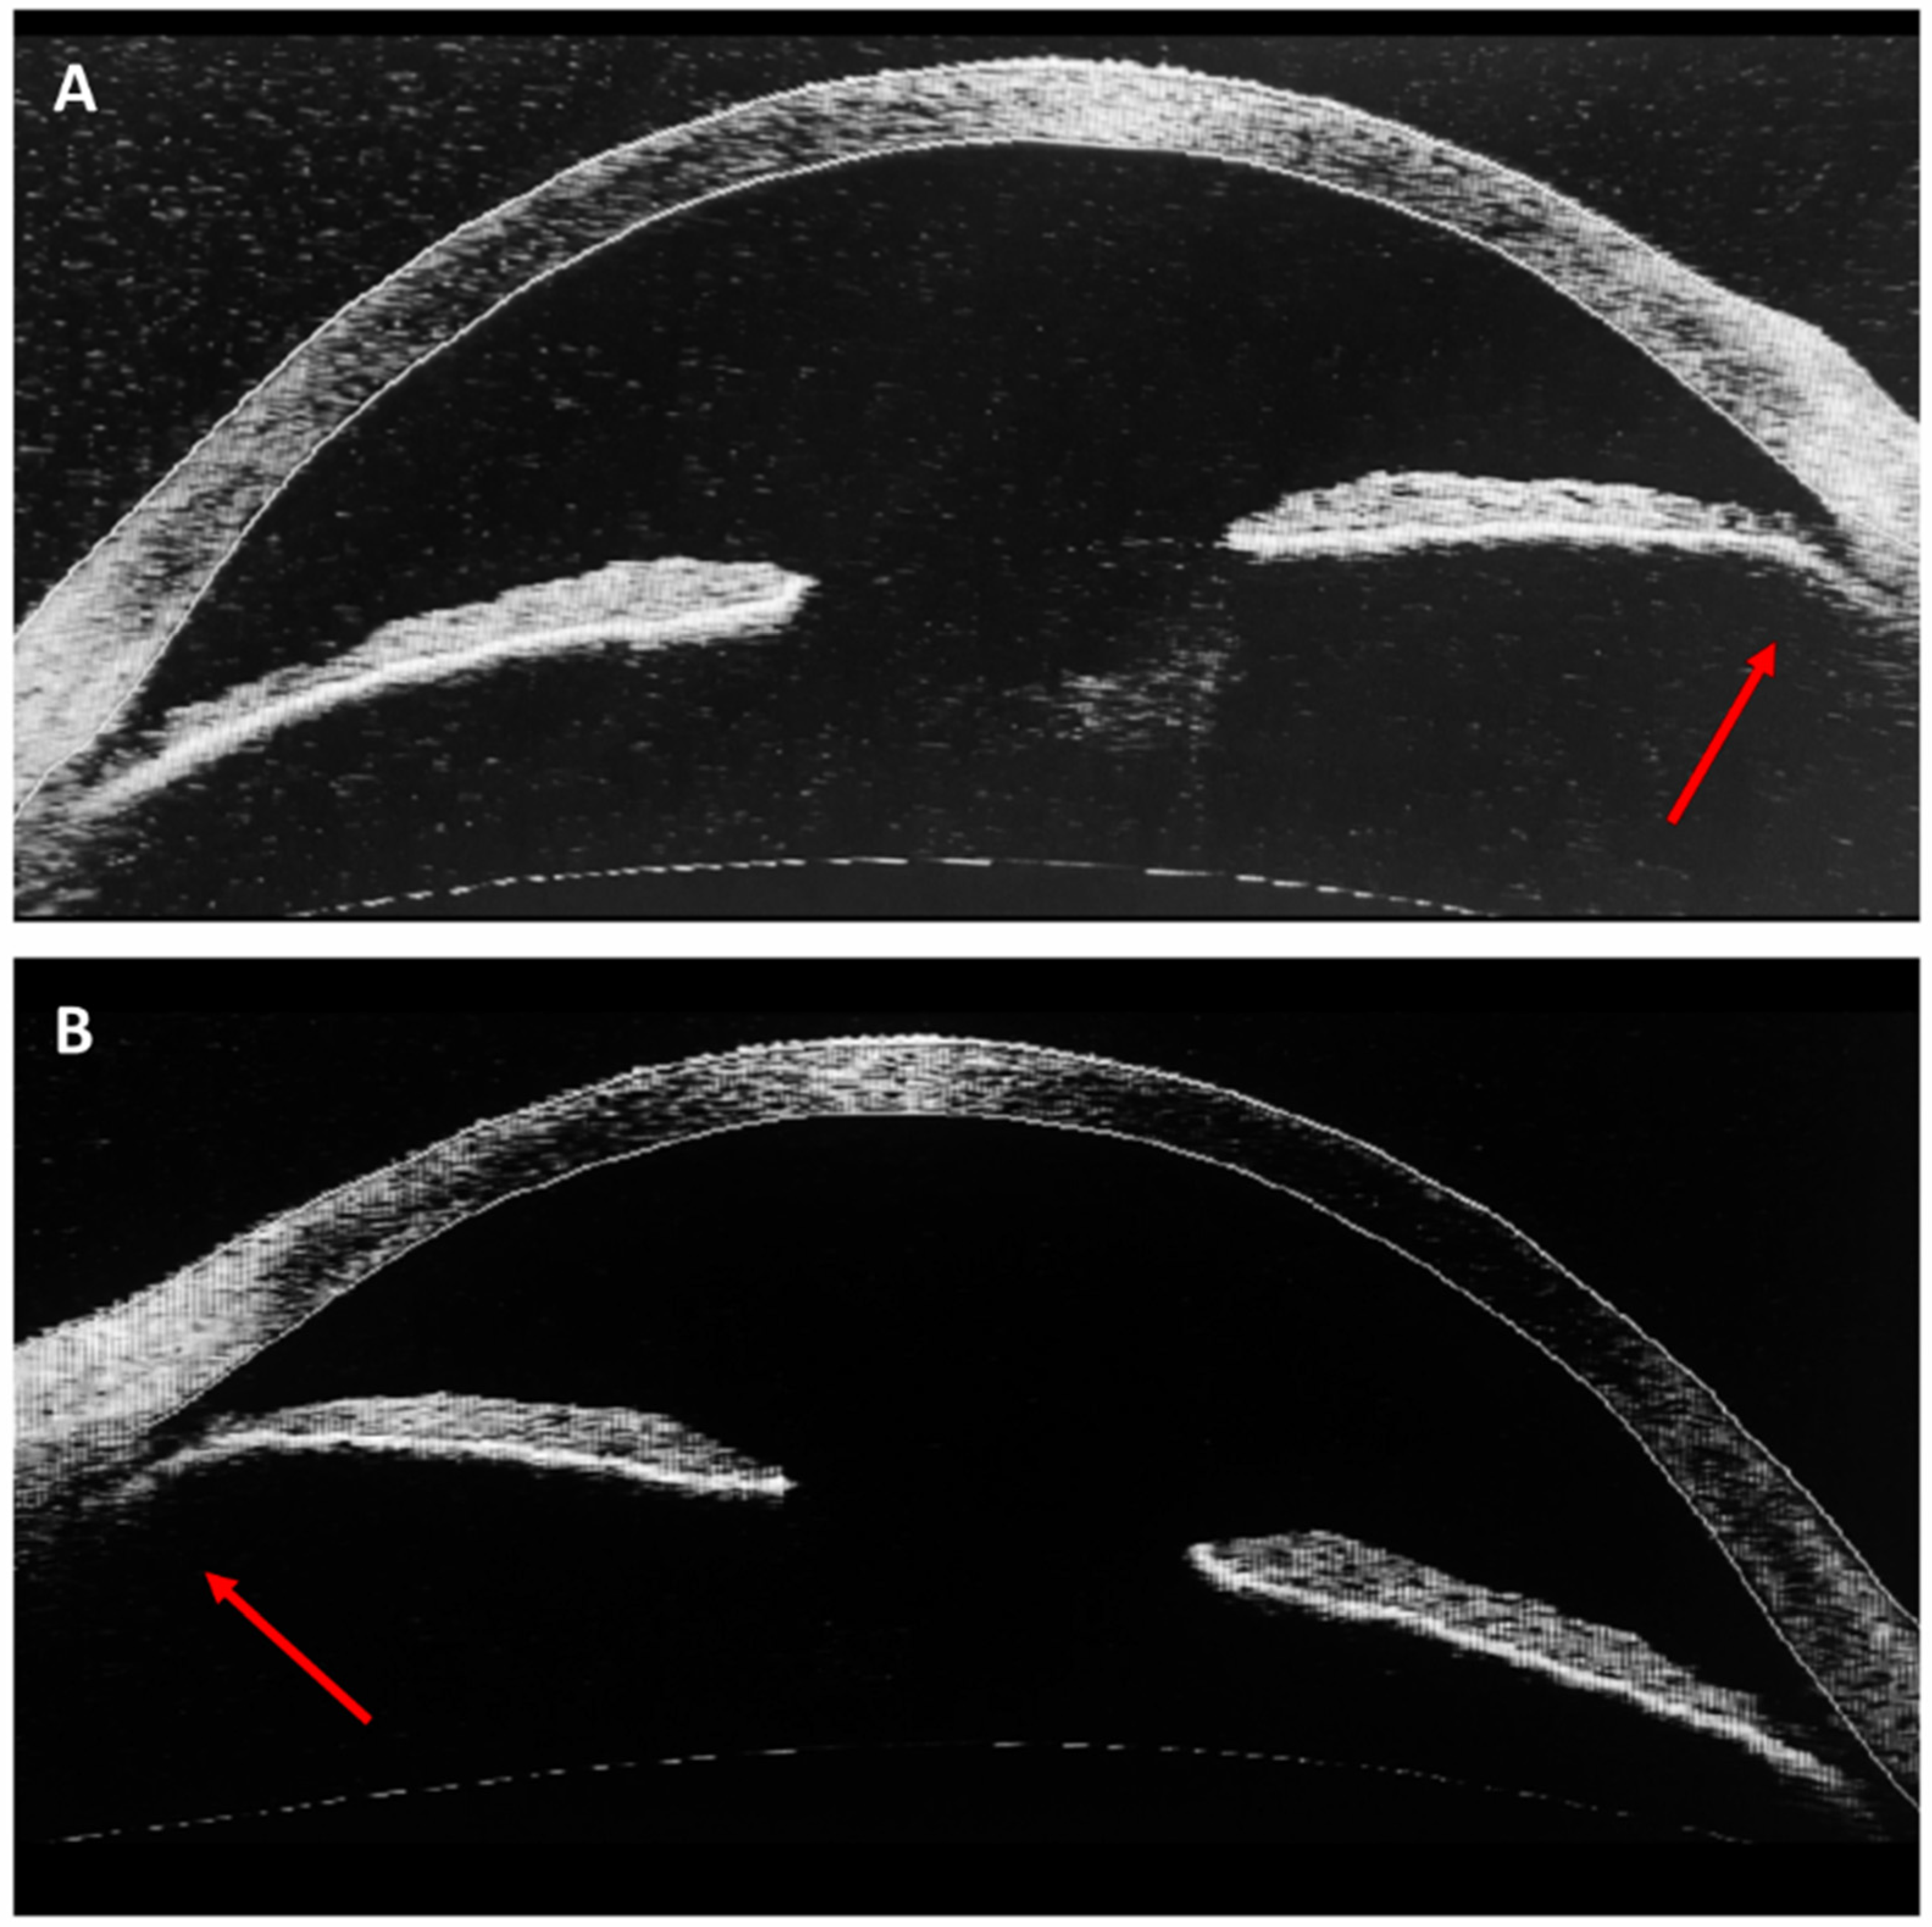

3. Case Report